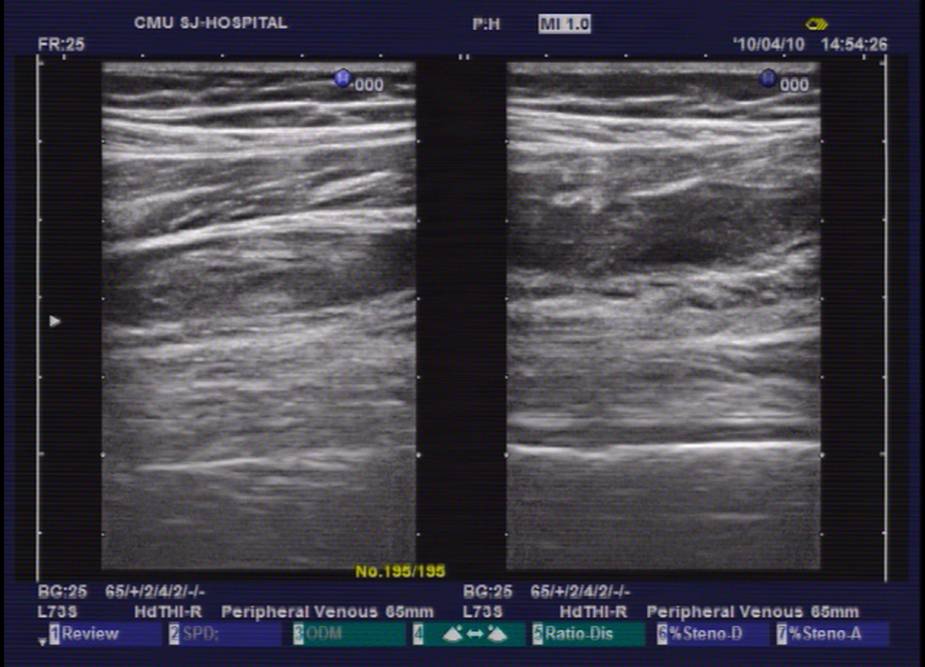

超声图像2

患者女性,52岁,因右膝关节疼痛2月为主诉入院。入院根据病史、查体和X线片诊断为右膝骨关节炎,经常规入院检查,未发现手术禁忌症,在硬膜外麻醉下行关节镜清理手术。术中应用止血带止血,手术过程顺利,手术时间为35分钟。术后给予弹力绷带包扎右下肢,术后第一天即嘱病人下地活动,疼痛较术前明显好转。术后给予了抗生素等药物,但未应用抗凝药物。术后第三天,患者出现右下肢肿胀、胸痛、呼吸困难,经行下肢超声和肺CT检查,结合血气分析等指标,呼吸科诊断为右下肢深静脉血栓形成,肺栓塞,转入呼吸科治疗。经溶栓、抗凝、支持等治疗2周后,病情痊愈出院。出院后继续服用华法林,定期检查凝血功能,维持INR值在1.5-1.5。